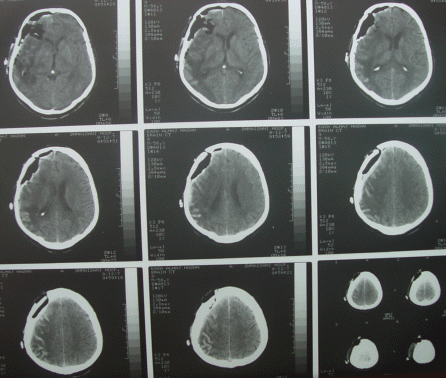

The patient in next postoperative day 09-December-2007 doing well and control CT-scan done showing the resection limits and the Gliadel wafers in the cavities.

The vital signs are stable and the patient using the T-piece with Venturi 50 and SO2 99% with pH 7.41 and pCO2 31 and pO2 97 mm Hg and he is convulsion free.

The patient showed steady improvement and the tracheostomy was removed 15-December-2007 and started normal feeding and MRI performed 23-December-2007 showed halt of the aggressive growth of the tumor.